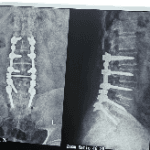

جراح مغز و اعصاب و ستون فقرات.دیسک کمر و دیسک گردن .عصب سیاتیک.درمان شکستگی مهره ها و جراحی تومورهای مغز و نخاع.درمان کمر درد و درد گردن مزمن لیزر دیسک کمر بدون نیاز به جراحی باز..تزریق داخل کمر.تزریق اینترا فورامینال و اعمال کم تهاجمی ستون فقرات.

گالری